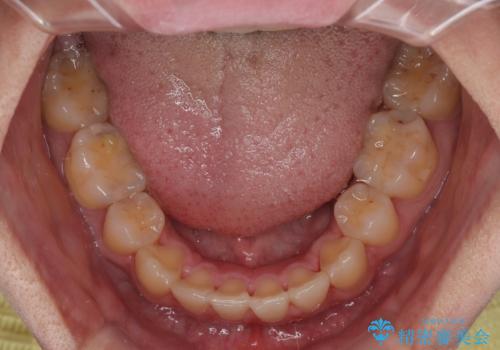

- 高校生の時に行った抜歯矯正の後戻りを気にして来院された患者様です。

インビザラインでの治療を希望されていて、デコボコの程度が中等度であり、安価なパッケージにて対応可能と判断されたため、インビザライン・モデレートを用いて矯正治療を行うこととしました。